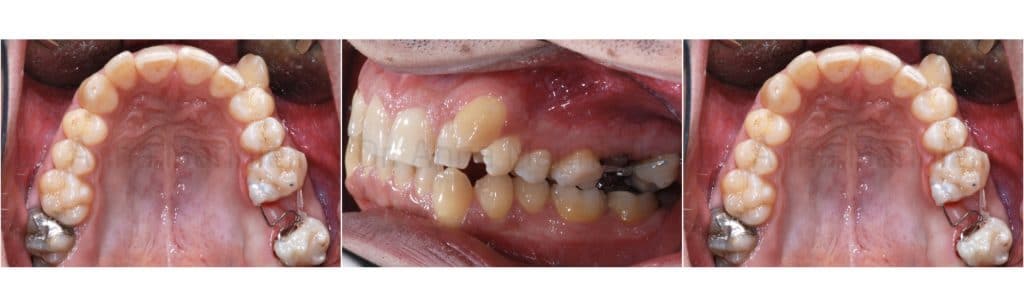

The following photos were taken at the end of distalization from 24 to 26 and alignment:

Final orthopantomography

Final teleradiography Cephalometric tracing